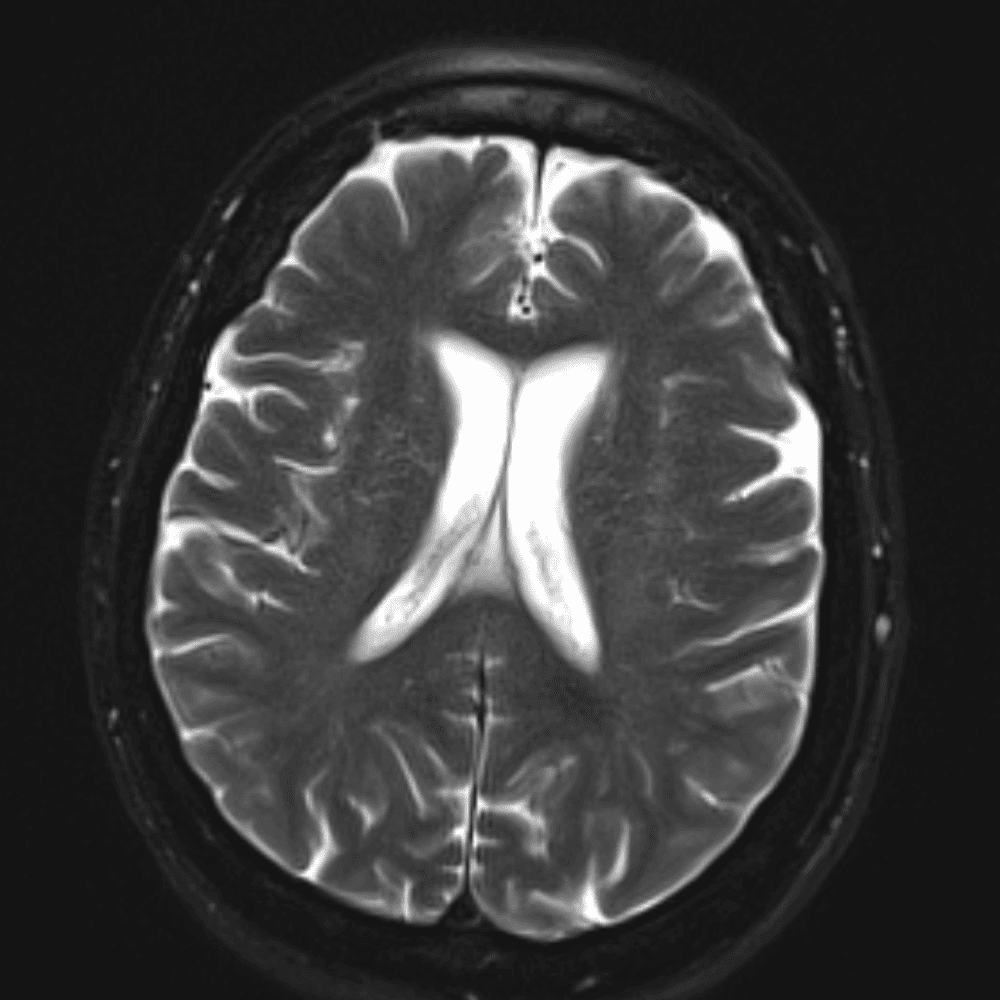

๋‹น์ง ์‹œ ํ”ํžˆ ๋ณผ ์ˆ˜ ์žˆ๋Š” ์‚ฌ๋ก€์˜ ์ „ํ˜•์ ์ธ ์˜ˆ๋ฅผ ํฌํ•จํ•ฉ๋‹ˆ๋‹ค.

39 ์‚ฌ๋ก€

์—ฐ์Šต

๋ฏธ๋ฌ˜ํ•˜๊ฑฐ๋‚˜ ์–ด๋ ค์šด ์‚ฌ๋ก€์™€ ์ผ๋ถ€ ์ •์ƒ ์‚ฌ๋ก€๋ฅผ ํฌํ•จํ•˜์—ฌ ๋‹น์ง์„ ์‹œ๋ฎฌ๋ ˆ์ด์…˜ํ•ฉ๋‹ˆ๋‹ค.

50 ์‚ฌ๋ก€